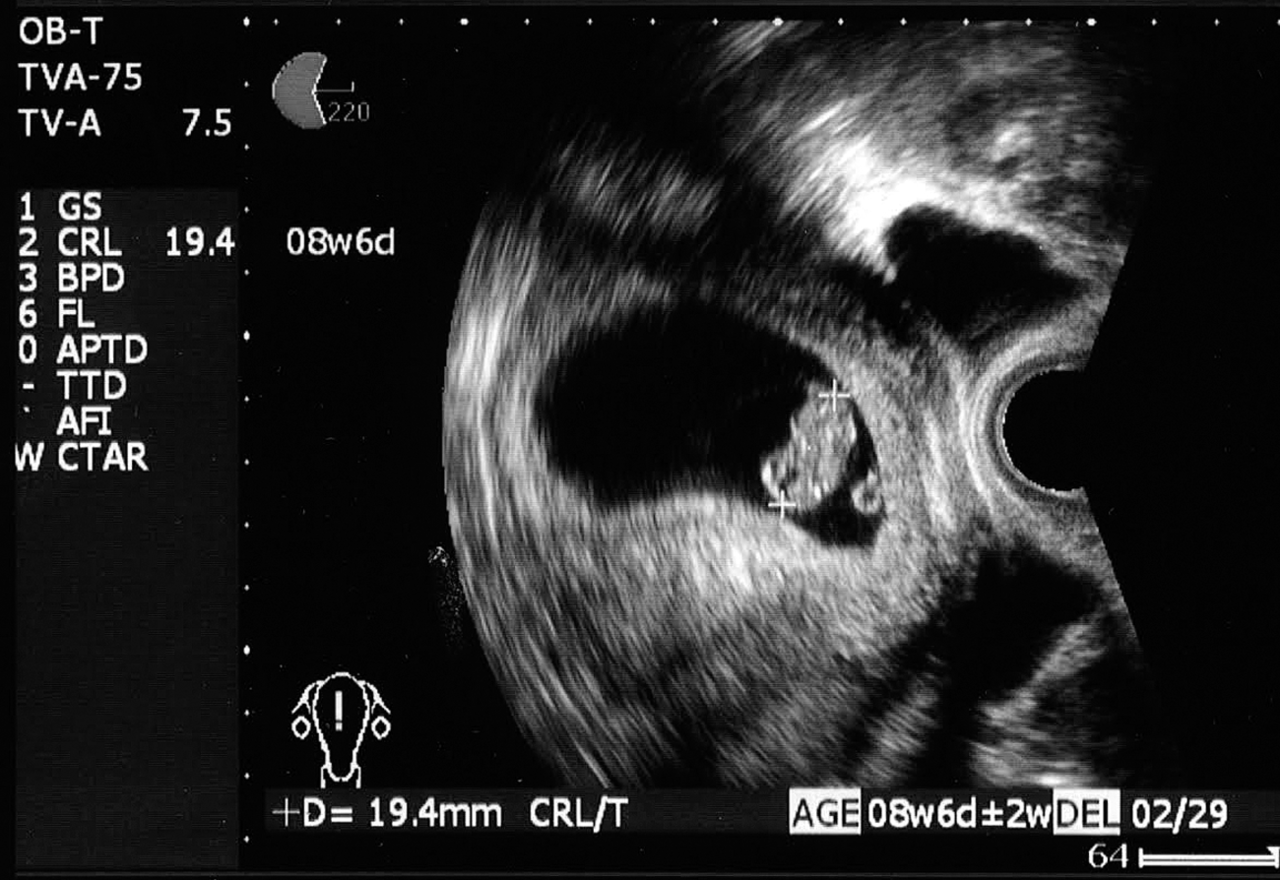

妊娠8週胎児 頭臀長19mm